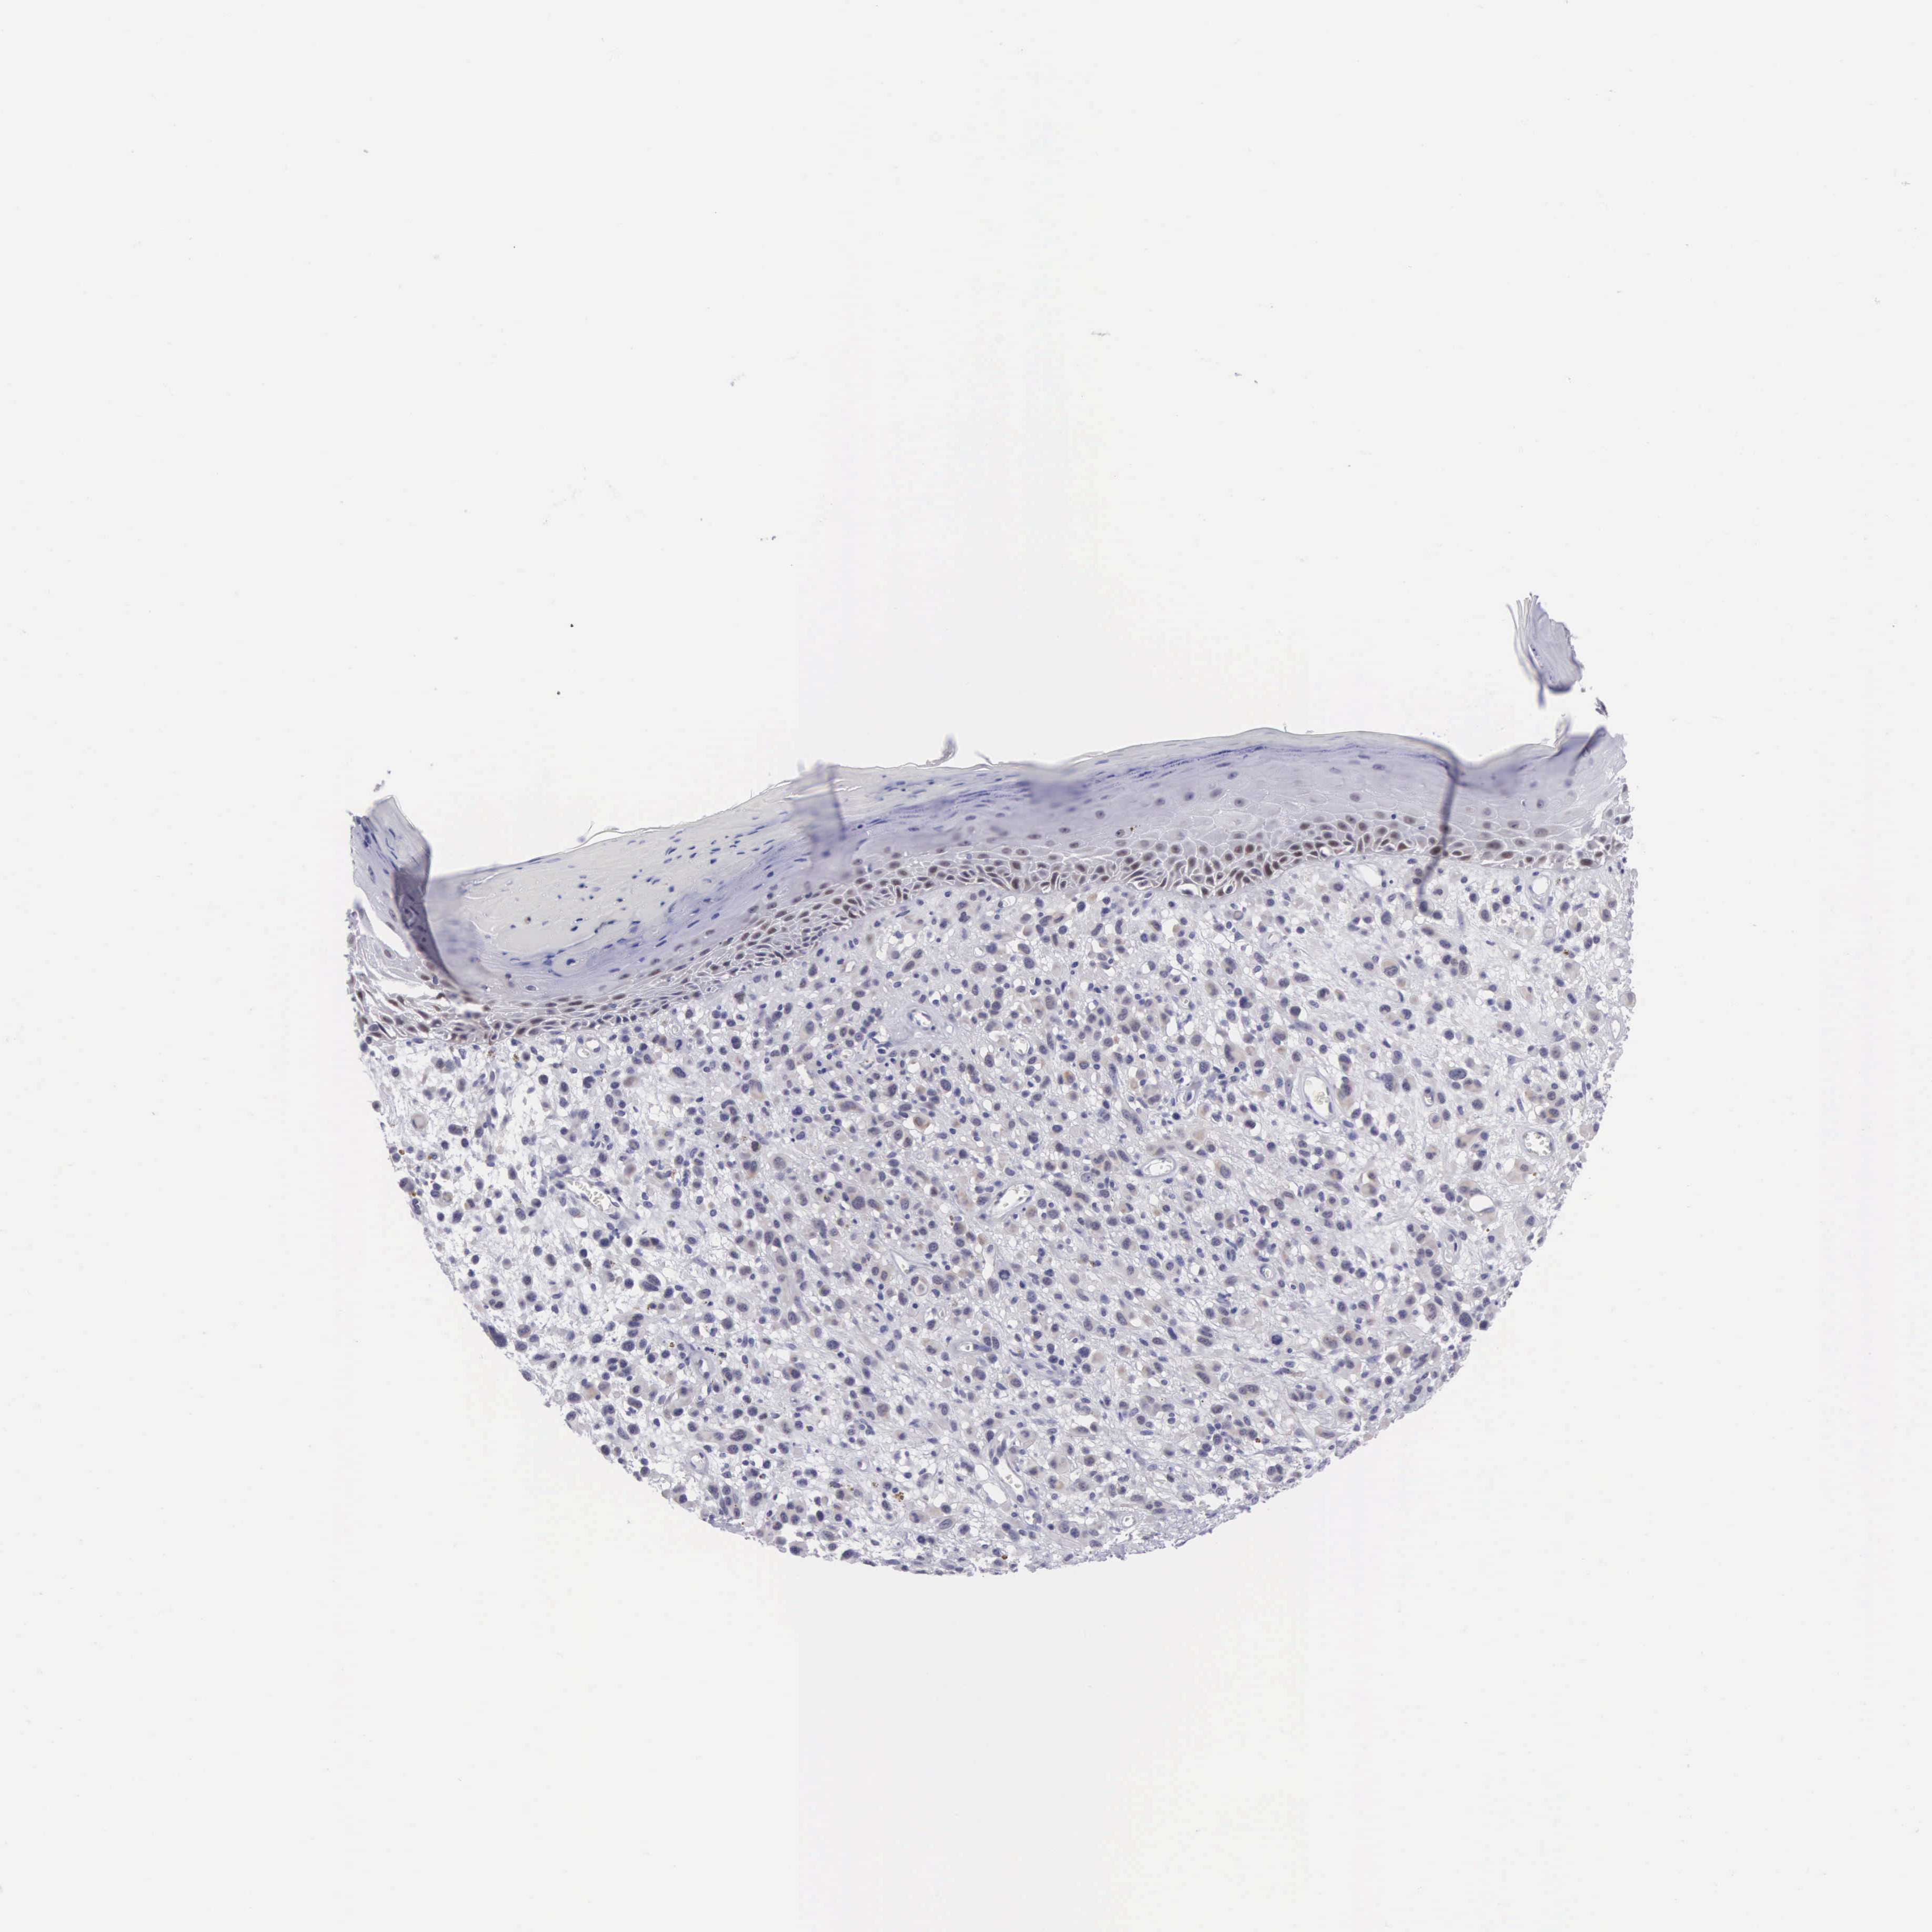

MELANOMA - Protein expressioni

A mouse-over function shows sample information and annotation data. Click on an image to view it in a full screen mode. Samples can be filtered based on level of antibody staining by selecting one or several of the following categories: high, medium, low and not detected. The assay and annotation is described here.

Note that samples used for immunohistochemistry by the Human Protein Atlas do not correspond to samples in the TCGA dataset.

Antibody stainingi

Antibody staining in the annotated cell types in the current human tissue is reported as not detected, low, medium, or high, based on conventional immunohistochemistry profiling in selected tissues. This score is based on the combination of the staining intensity and fraction of stained cells.

Each image is clickable and will lead to virtual microscopy that enables deeper exploration of all samples and also displays staining intensity scores, fraction scores and subcellular localization as well as patient and tissue information for each sample.

Antibody HPA000536

Antibody CAB056152

Antibody CAB056153

Staining

High

Medium

Low

Not detected

Intensity

Strong

Moderate

Weak

Negative

Quantity

>75%

75%-25%

<25%

None

Location

Nuclear

Cytoplasmic/membranous

Cytoplasmic/membranous,nuclear

Malignant melanoma, NOS

Malignant melanoma, Metastatic site